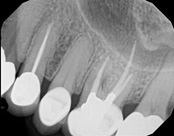

The patient presented with mild pain, a cavity, and a broken filling was evident. After performing diagnostic testing, the diagnosis was: irreversible pulpitis, symptomatic periradicular periodontitis. Root canal therapy was done and the tooth healed well and is still functioning.